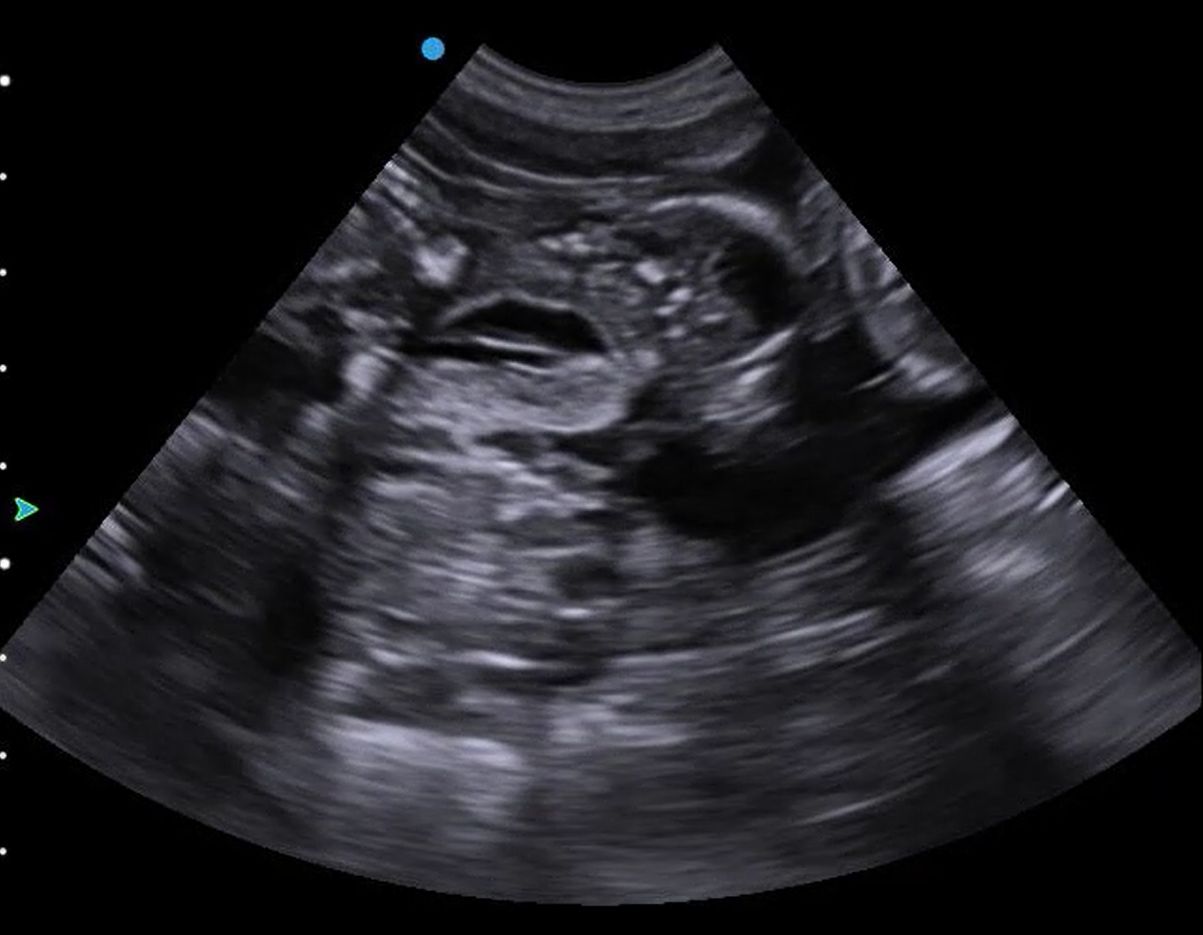

Wire haired fox terrier day 35 (40 days from last tie) good example of how sperm can hang around awhile before fertilisation occurs . Gestational sacs developing well just not